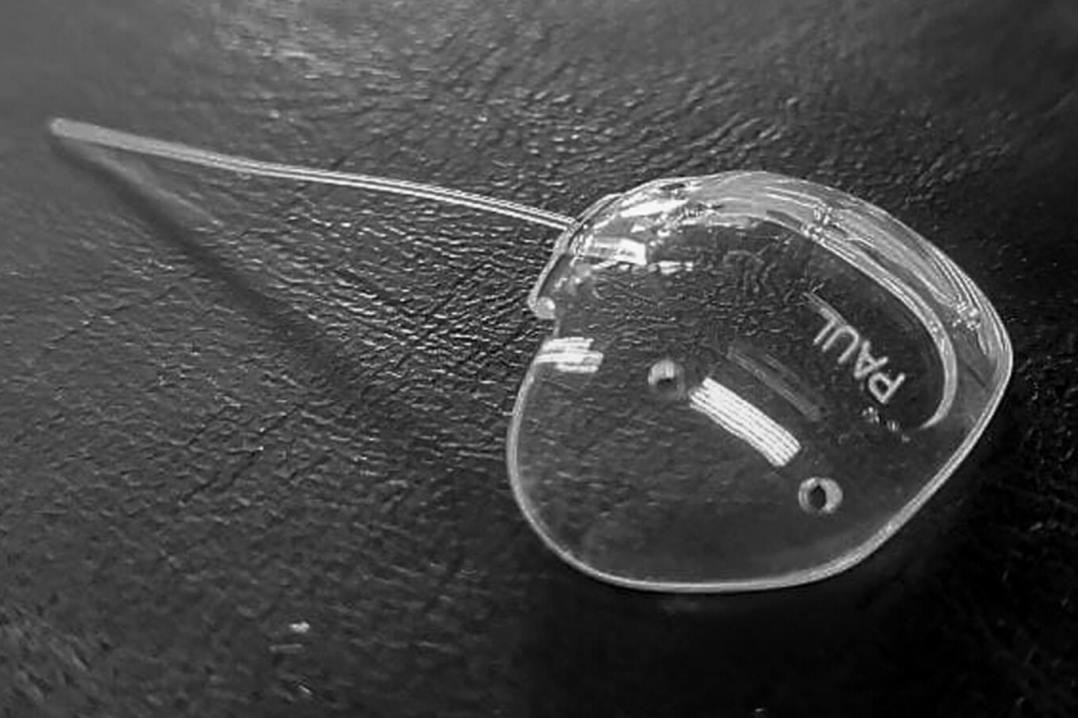

3. Pneumatic displacement using intravitreal anti-VEGF, tissue plasminogen activator (tPA) and gas

Pneumatic displacement of submacular haemorrhage away from the fovea was described by Heriot in 19965. It involves lysing the submacular haemorrhage clot with intravitreal injection of tPA (eg. alteplase) and 0.3-0.5ml of expansile gas (typically 100% SF6 or C3F8) to ‘push’ the haemorrhage away from fovea. Anti-VEGF is usually given at the same time to treat the underlying CNVM and, with the injection volume required, anterior chamber (AC) paracentesis is performed one or more times to maintain optic nerve head perfusion. Injection should be performed in a clean room using routine intravitreal injection protocol, with a dilated pupil to allow visualisation of the gas bubble and to check optic nerve head perfusion post-procedure. A rise in intraocular pressure (IOP) is expected but typically equilibrates over several hours. Non-contact IOP methods, such as iCare, can be inaccurate after AC paracentesis and with gas in the eye. Numerous combinations of doses, types of gas and addition of anti-VEGF have been made and these have shown various results3. Ideal candidates are those with recent onset (< 2 weeks) of mainly subretinal haemorrhage under the fovea or inferior macula, with the ability and willingness to posture following the procedure. SMH relatively superior to fovea may be a contraindication, as displacement could lead to haemorrhage being moved under the fovea. This technique is generally felt to be ineffective for pure sub-RPE haemorrhage. Posturing is either commenced immediately after the procedure or in the first 24 hours to allow dissolution of the clot. Strategies include partial or full face-down positioning.